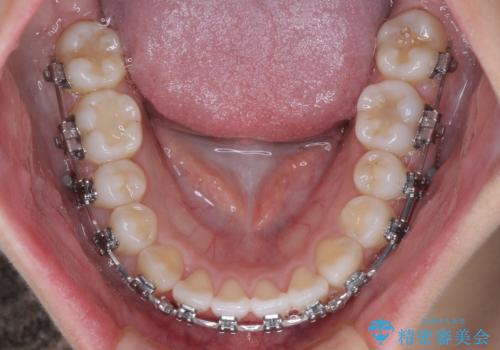

- 矯正装置

- メタルブラケット

- 治療期間

- 1年2ヶ月

マウスピース矯正での自己管理の煩わしさが気になる方には、ワイヤー矯正がおすすめです。